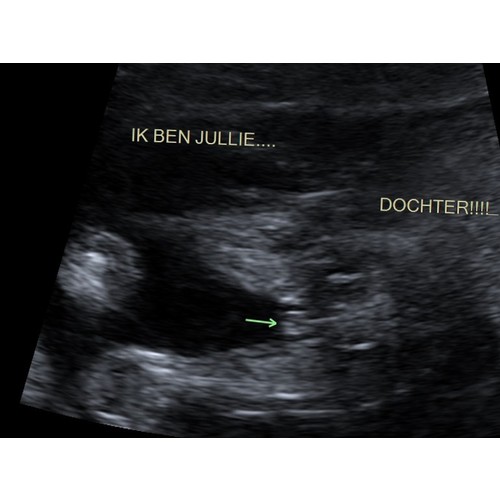

Bij ons werd uitgelegd dat wanneer de streepjes naar binnen gaan t een meisje is, en als je een uitstulping ziet het een jongen is.. lijkt mij op deze echo heel duidelijk een meisje !

een meid denk ik hoor, je ziet echt 2 strepen zo was het bij alle 3 mijn meiden. gefeliciteerd!

Ik denk dat het inderdaad een meisje is.